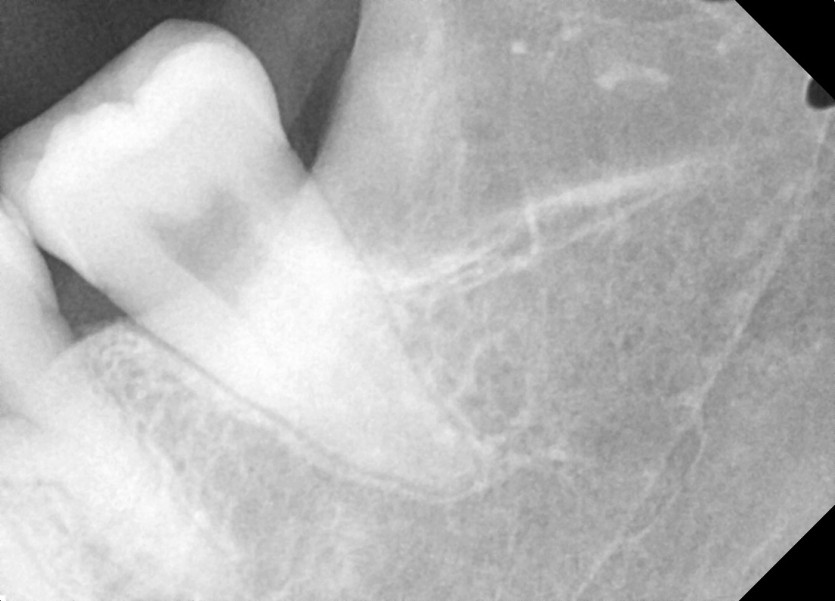

#28,38 사랑니 발치

구강 외과 전문의가 당일 발치했습니다.